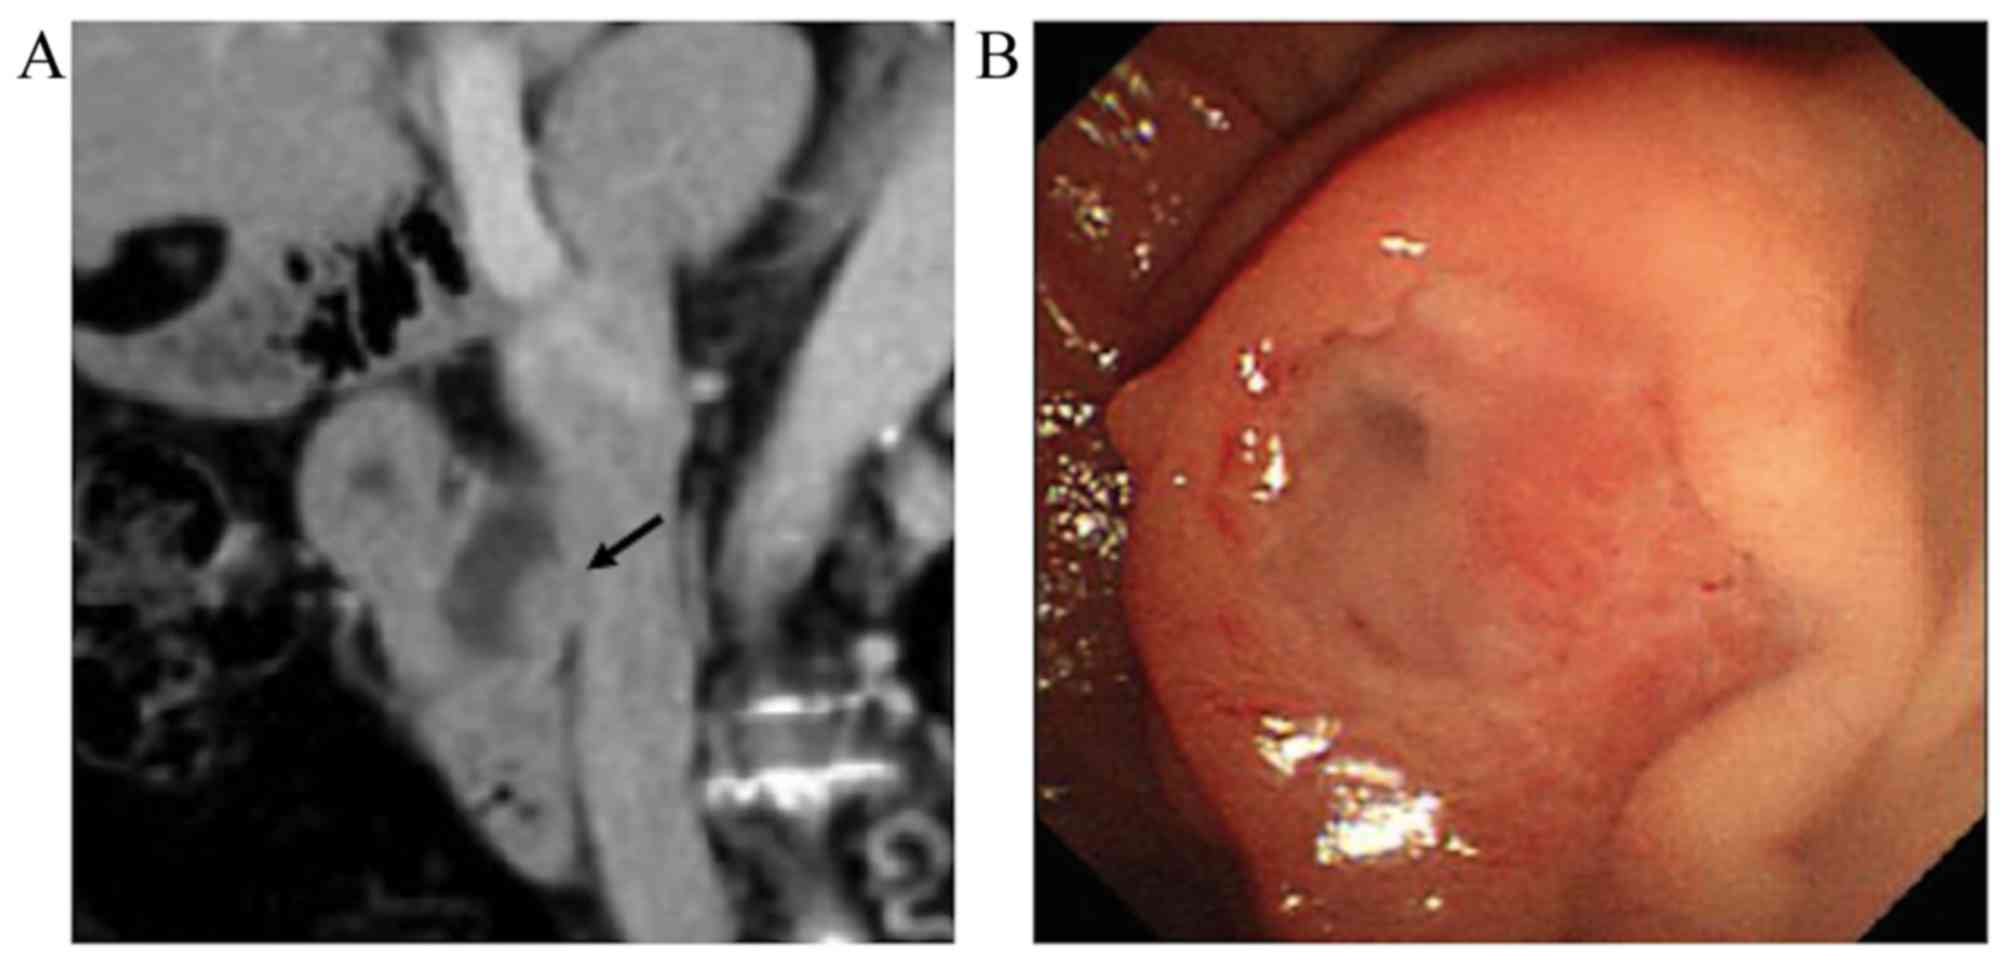

A 64-year-old woman with no particular previous medical history presented with fever lasting for 1 week. No remarkable findings were noted in a physical examination. The serological tests revealed elevated levels of C-reactive protein (13.4 mg/dl; normal range, <0.5 mg/dl), alanine aminotransferase (62 IU/l; normal range, 5–36 IU/l), alkaline phosphatase (816 IU/l; normal range, 110–370 IU/l) and γ-glutamyl transpeptidase (360 IU/l; normal range, 9–50 IU/l). The leukocyte count and serum levels of aspartate aminotransferase, total bilirubin, carcinoembryonic antigen and carbohydrate antigen 19–9 were within the normal range. On computed tomography (CT), a 75-mm cystic mass in the right hepatic lobe and dilatation of the intrahepatic bile duct were detected (Fig. 1A). Following aspiration due to a suspected infectious liver cyst, the patient underwent endoscopic retrograde cholangiography (ERC), which revealed filling defects within the dilated common hepatic duct (Fig. 1B). On peroral cholangioscopy (POCS), a papillary mucin-producing tumor was identified around the orifice of the right hepatic duct, while no obvious tumor was present in the left hepatic and common bile ducts (Fig. 2). Although the small bile duct biopsy from the papillary tumor was not conclusive, extended right hepatectomy was performed for suspected IPNB. On intraoperative frozen section examination, the common hepatic duct margin was tumor-free, while the left hepatic duct appeared to be positive for an intraepithelial tumor with high-grade dysplasia. Despite additional resection of the left hepatic duct, the final resection margin remained focally positive for an intraepithelial neoplasm.

Figure 1.

Findings on contrast-enhanced computed tomography (CT) and endoscopic retrograde cholangiography (ERC). (A) Contrast-enhanced CT (coronal image) showing a 75-mm cystic mass in the right hepatic lobe and dilatation of the intrahepatic bile duct. (B) ERC showing a filling defect in the common duct (arrow). The cyst is not visible, as it was aspirated prior to ERC.